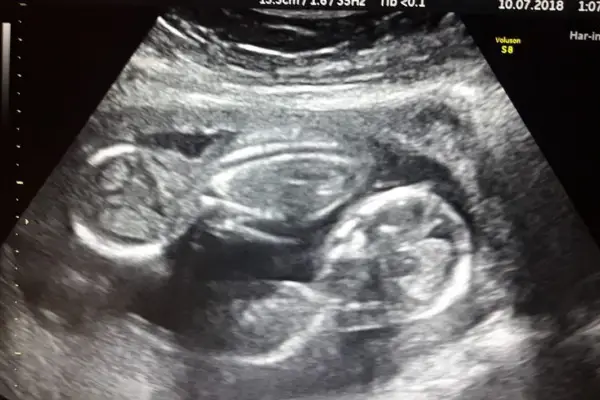

Nacieron trigemelas en Chubut: cuáles son las características de un embarazo múltiple

Cuáles son las causas y por qué se consideran de riesgo los embarazos múltiples.